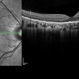

- macula serpiginous choroidopathy

- Tom Steele, CRA

TRC 50ex - Description

- 10/21/2009